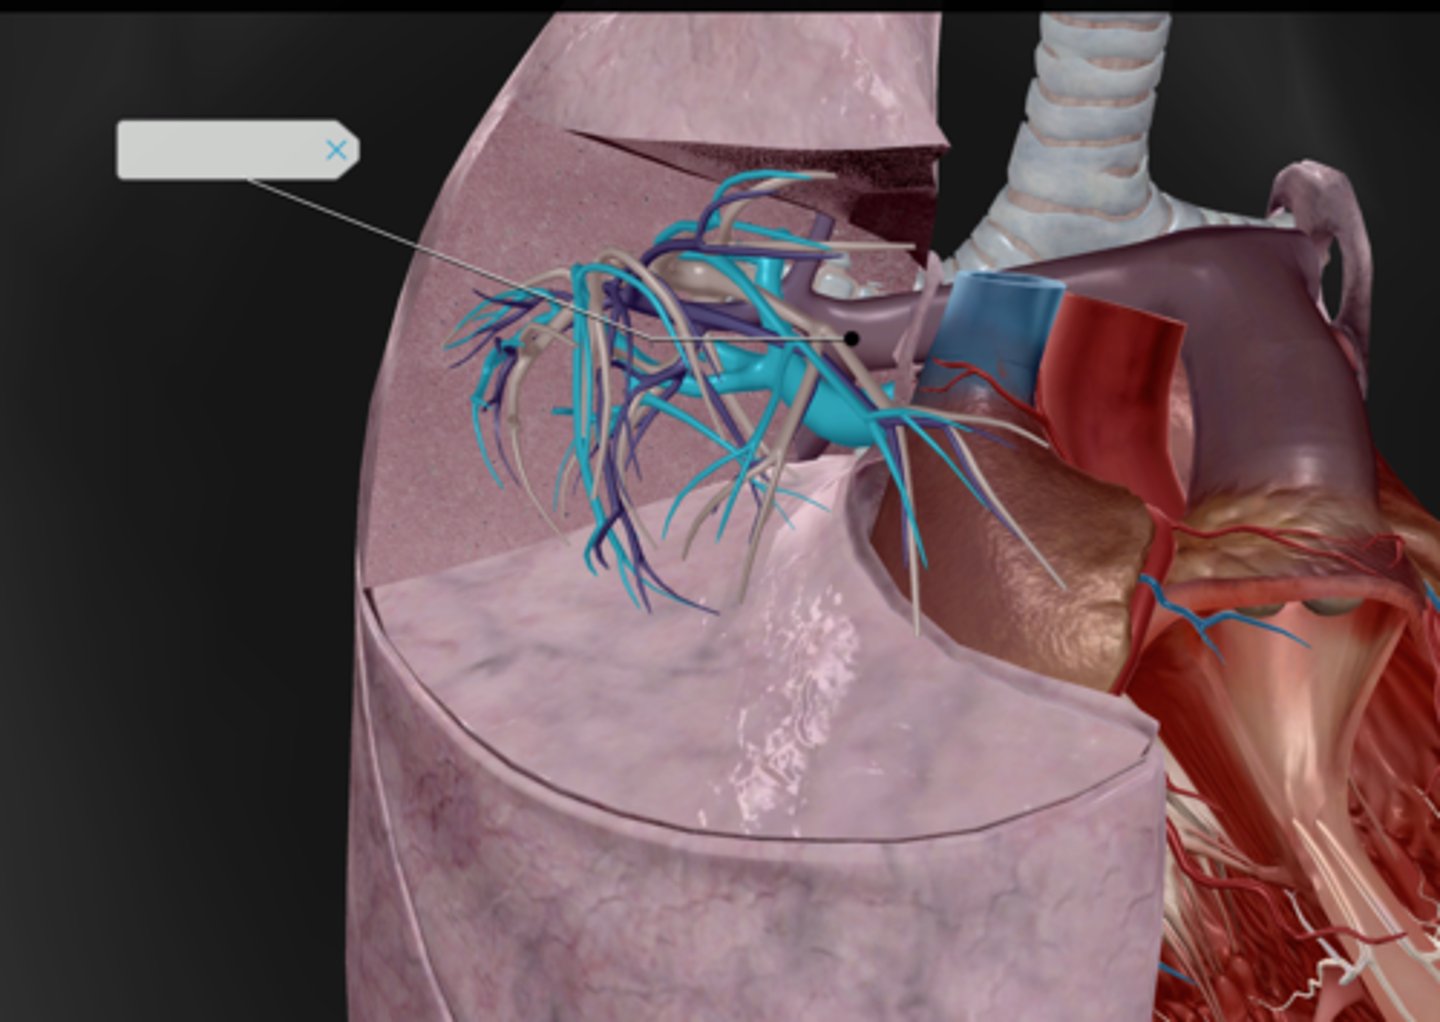

Primary bronchus

Secondary bronchi

Any of the tertiary bronchi

Bronchioles

Hilum

Pulmonary arteries

Pulmonary veins